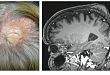

2021.01.05 今日病例:持续 70 年的头皮包块

您考虑什么?

2020.12.15 这种脱发不是斑秃,而是淋巴瘤

一文了解亲毛囊性蕈样肉芽肿所致淋巴瘤性脱发。